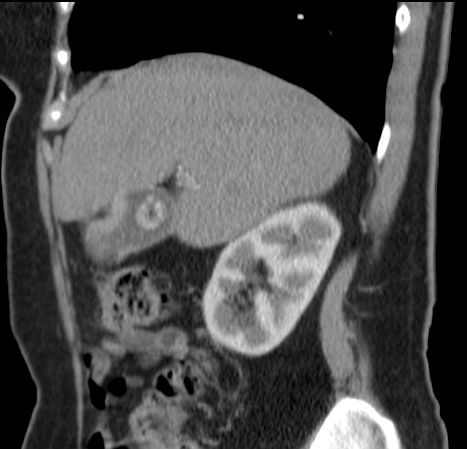

89-jährige Frau mit Infektzeichen. Zunächst sonographisch Verdacht auf Gallenblasenempyem. Im CT ein Gallenblasenkarzinom mit Leberinfiltration. Wegen Alter und AZ palliative Versorgung. | ||